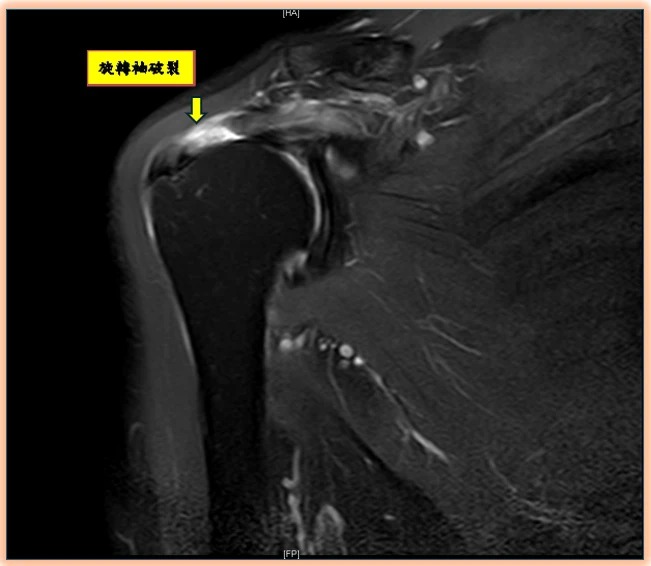

旋轉肌袖破裂如何診斷?陳昱彰表示,起初常被誤認為肌腱拉傷或五十肩,但症狀久未改善時,應盡早請骨科醫師進行正確診斷與治療。診斷方式除理學檢查、X光、超音波外,也常以核磁共振(MRI)確認破裂程度與型態,作為手術規劃依據。